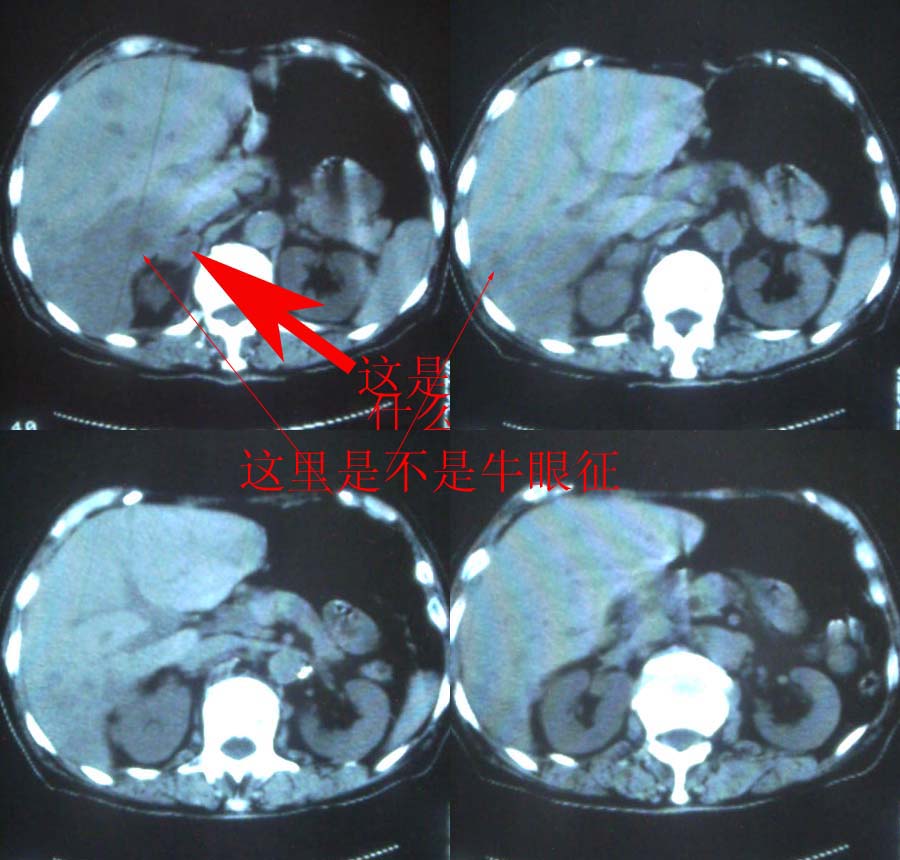

再者,肝的转移灶一般显示为多发性大小不等的低密度肿瘤结节,也可为单发结节。多在低密度病变内存在更低密度区域,从而显示为同心圆状或等高线状双重轮廓--即牛眼为其特征。本例肝右叶后段的大块状病灶无论形态、密度均不具备转移灶的特点。

关于牛眼征我记得好象是血液供应不上而坏死吧?其并不是肝转移瘤专利。

看看下面是不是牛眼征: